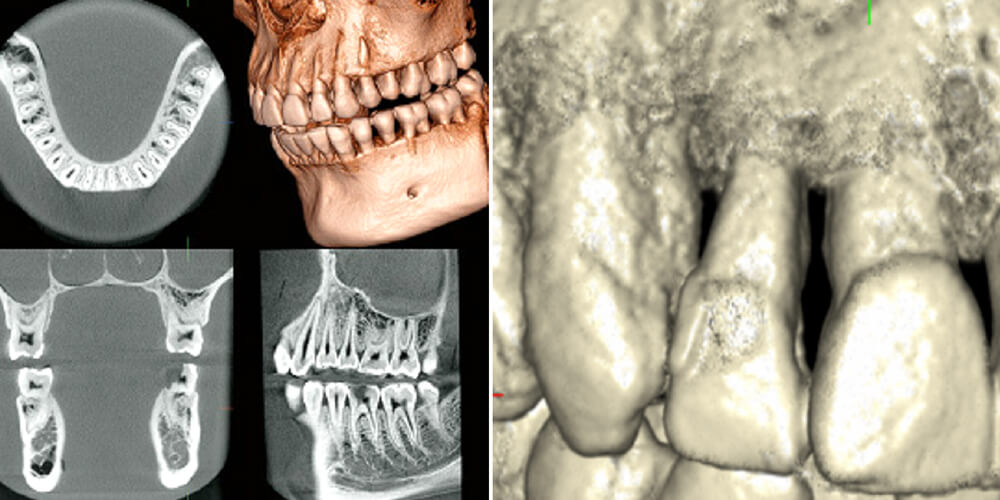

歯科用CTの活用

歯周病は骨が溶ける病気ですが、そうお伝えしたところで自覚症状がなければなかなか実感が湧かないものです。

当院ではCT(歯科ドック)により、骨の溶け具合を「可視化」してお伝えします。

このように、レントゲン画像だけでは伝えきれない情報をわかりやすく患者様にお届けすることは、当院の考える「インフォームド・コンセント」の1つのカタチでもあります。